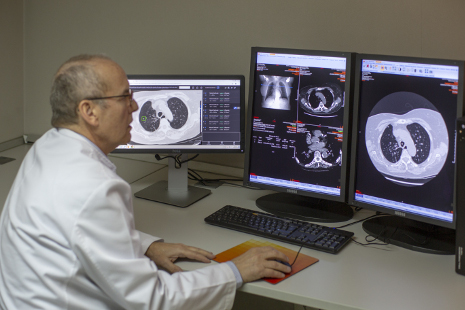

Una vez que la inteligencia artificial, analizó más de 42 mil 290 tomografía digitales de pulmón, el desafío fue comparar los resultados obtenidos, con el diagnostico de seis radiólogos. Para sorpresa de todos, el programa pudo identificar tumores de cáncer de pulmón, con mayor eficacia que los médicos.

El Prof. Mozziyar Etemadi, coautor del estudio explica que no se trata de ningún milagro, la verdadera razón por que la AI en 3D puede realizar un mejor diagnóstico, es porque los radiólogos muchas veces se llegan a contaminar visualmente de tantos contrastes que ven diariamente.

“La AI en 3D puede ser mucho más sensible en su capacidad para detectar el cáncer de pulmón temprano que el ojo humano al ver imágenes en 2D. Esto es técnicamente “4D” porque no solo se trata de una tomografía computarizada, sino de dos (la exploración actual y la anterior) a lo largo del tiempo “, detalló.